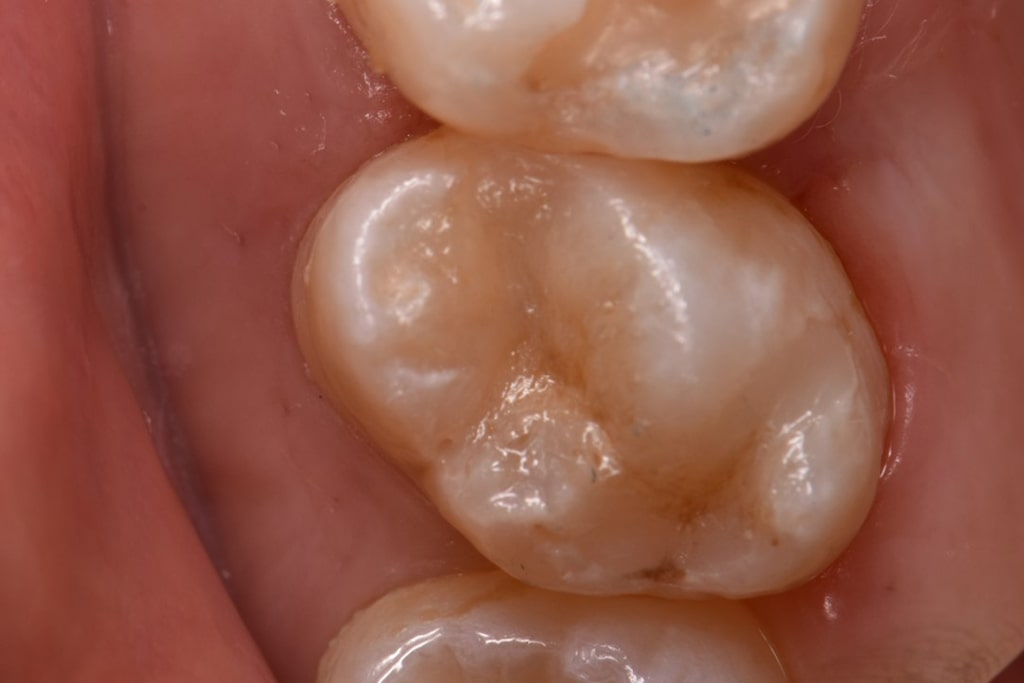

「噛むと痛い」という24歳女性の患者さまの場合

「噛むと痛い」という

24歳女性の患者さまの場合

修復

削った部分を修復して、治療完了です。

プラスチック素材とセラミック素材を混合した「ハイブリッドレジン」という素材を、歯の表面に盛りつけて形を整えます。

これは「ダイレクトボンディング」という治療法で、白い素材で見た目が自然に仕上がり、型取りなどの手間と時間がかかりません。

※ダイレクトボンディングは自由診療です。治療費用33,000円

※削る部分が大きすぎるなど、症例によって適応できない場合があります。